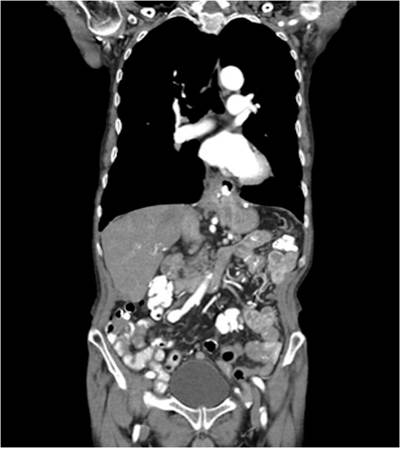

Ante la estabilidad del paciente, se decide hacer un estudio seriado de las vías digestivas altas, que evidencia el paso del medio de contraste sin reflujo, y una tomografía de tórax y de abdomen, que muestran cambios posquirúrgicos en la unión esofagogástrica con dilatación esofágica y retardo al paso de medio de contraste sin extravasación del mismo. En la Figura 2 se muestra el corte más representativo de la tomografía. Al no encontrar hallazgos que sugirieran perforación esofágica en los estudios practicados, se realizó una nueva endoscopia para intentar el corte y retiro de la malla.

Figura 2 Imagen del corte coronal de la tomografía toracoabdominal, en la que se evidencian cambios posquirúrgicos en la unión esofagogástrica con dilatación esofágica sin extravasación del medio de contraste.